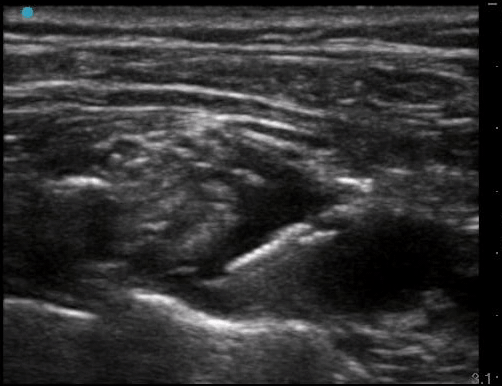

Supraclavicular Brachial Plexus block that was successful for a distal radius fracture